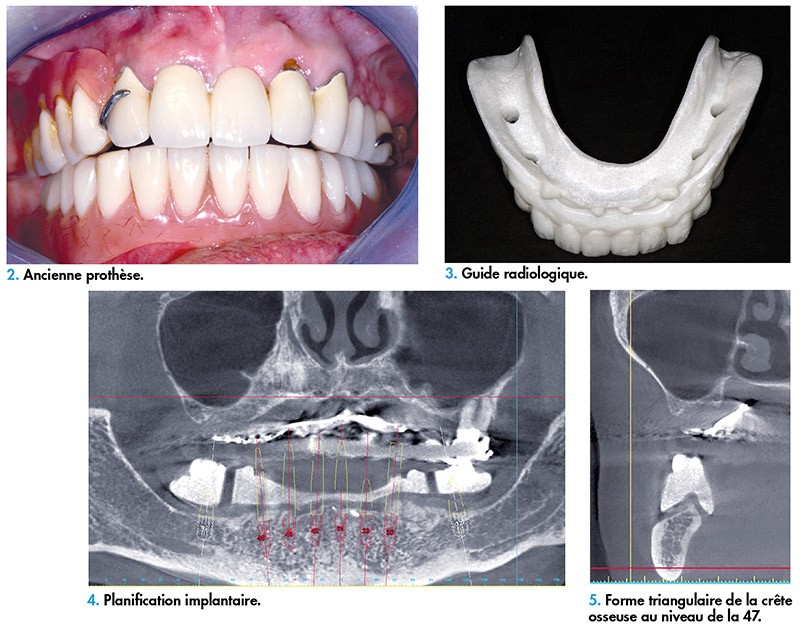

De ce nouveau montage découle une gouttière radiologique qui est la copie conforme de la prothèse d’usage (fig. 3). La planification est ensuite réalisée (fig. 4). Ici, il a été décidé d’anguler 35 et 45 en raison de la position des foramens mentonniers.

Il est facile d’estimer l’épaisseur gingivale présente et ainsi de choisir la hauteur du col du futur implant au niveau du secteur antérieur. En revanche, dans les zones postérieures, la forme de la crête osseuse nécessite la réalisation d’une plastie osseuse (fig. 5). L’incertitude d’obtenir une stabilité primaire suffisante dans le secteur postérieur nous conduit à préconiser une pose d’implants Axiom BL (implant sous-crestal ou juxta-osseux – Bone Level, Anthogyr) en deux temps opératoires. Dans les autres secteurs, des implants Axiom TL (implant transgingival – Tissue Level, Anthogyr) seront choisis, en raison de leur simplicité d’utilisation dans la gestion prothétique.